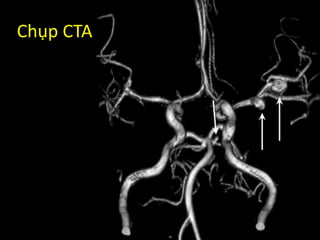

Chụp CTA

Ct in-stroke

• Một namthanh niên 25 tuổi, tiền sử đau nửa đầu 1 năm nay, đang chạy thể dục buổi sáng bỗng thấy đau đầu dữ dội (anh ta khẳng định “Chưa thấy khi mô mà đau đầu kinh khủng như ri hết a”). Anh ta ghé vào nhà người quen, uống 1 viên Paracetamol rồi được đưa vào viện. Trên đường đi, anh ta vẫn thấy đau đầu dữ dội, nôn thốc tháo, rồi thấy nhìn mờ, rồi lơ mơ … Case 2 – 30 chưa phải là Tết

• 81.

• Vào khoacấp cứu: Vẫn lơ mơ, GCS 11p, liệt tay chân (P), tay chân (T) còn đáp ứng với kích thích đau. Babinski (+) bên (P), cổ gượng nhẹ. • Mạch: 60; HA: 190/110; TST: 25 • Chẩn đoán sơ bộ? • Chỉ định xét nghiệm gì tiếp theo?

• 82.

Kết quả CTtrả về: BÌNH THƯỜNG

• 83.

Bạn có thayđổi chẩn đoán? So, what do you do next?

• 84.

• Kiểm soáthuyết áp • Chống phù não – Thở Oxy – Nằm đầu cao 20-300 – Truyền dịch ưu trương • Bác sĩ tiến hành chọc dịch não tủy Kết quả: 3 ống đều có màu hồng

• 85.

Chọc dịch nãotủy • Positive in:  100% in 12h to 2 weeks  >70% after 3 weeks  40% after 4 weeks